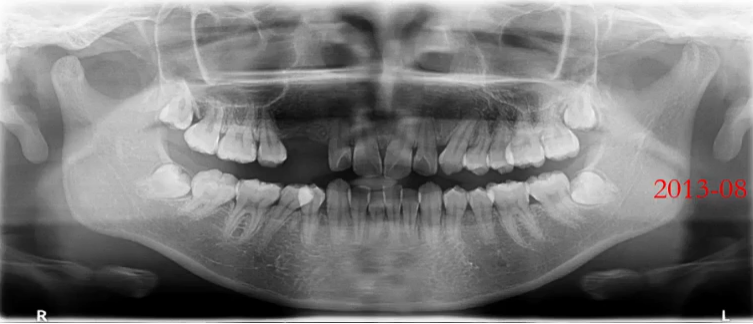

2. 混合牙列期:乳牙情况、恒牙胚观察

曲面断层片拍摄时体位相对比较简单,小患者的配合程度相对高一些。

上颌前牙区、下颌前牙区牙位辨认

患者处于混合牙列期,可以看到右侧前牙区有多生牙,下颌有融合牙的存在。